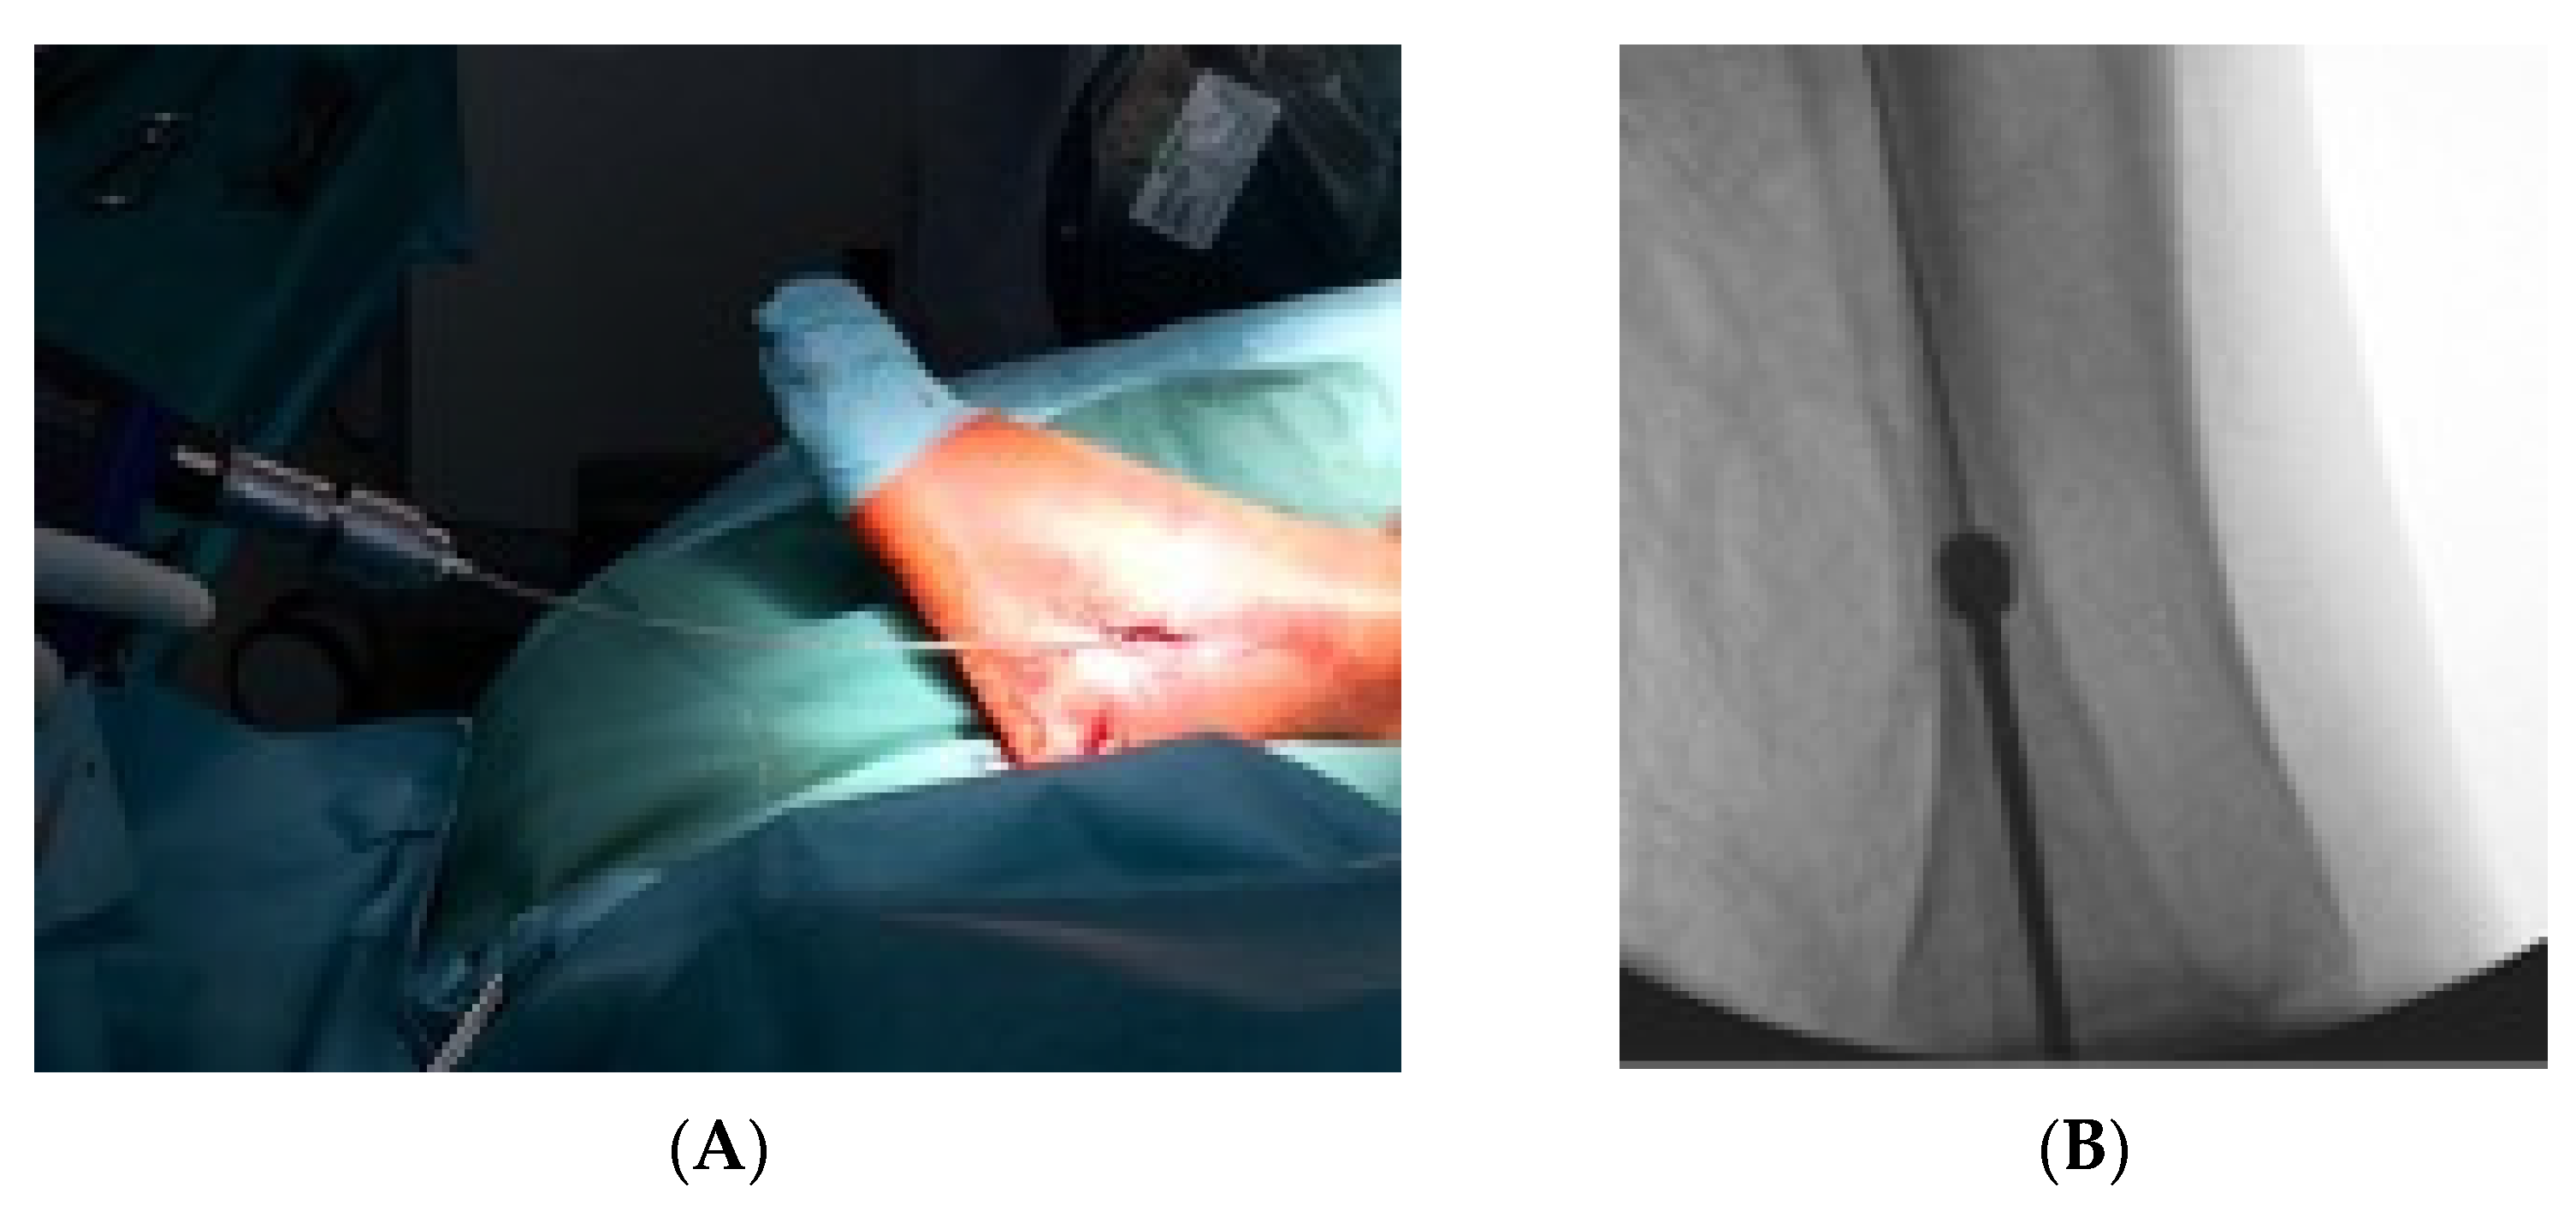

2.2. Surgical Technique and Postoperative Therapy

- Zyskowski, M.; Crönlein, M.; Heidt, E.; Biberthaler, P.; Kirchhoff, C. Osteosynthesis of distal fibular fractures with IlluminOss: Video article. Unfallchirurg 2017, 120, 6–11. [Google Scholar] [CrossRef][Green Version]